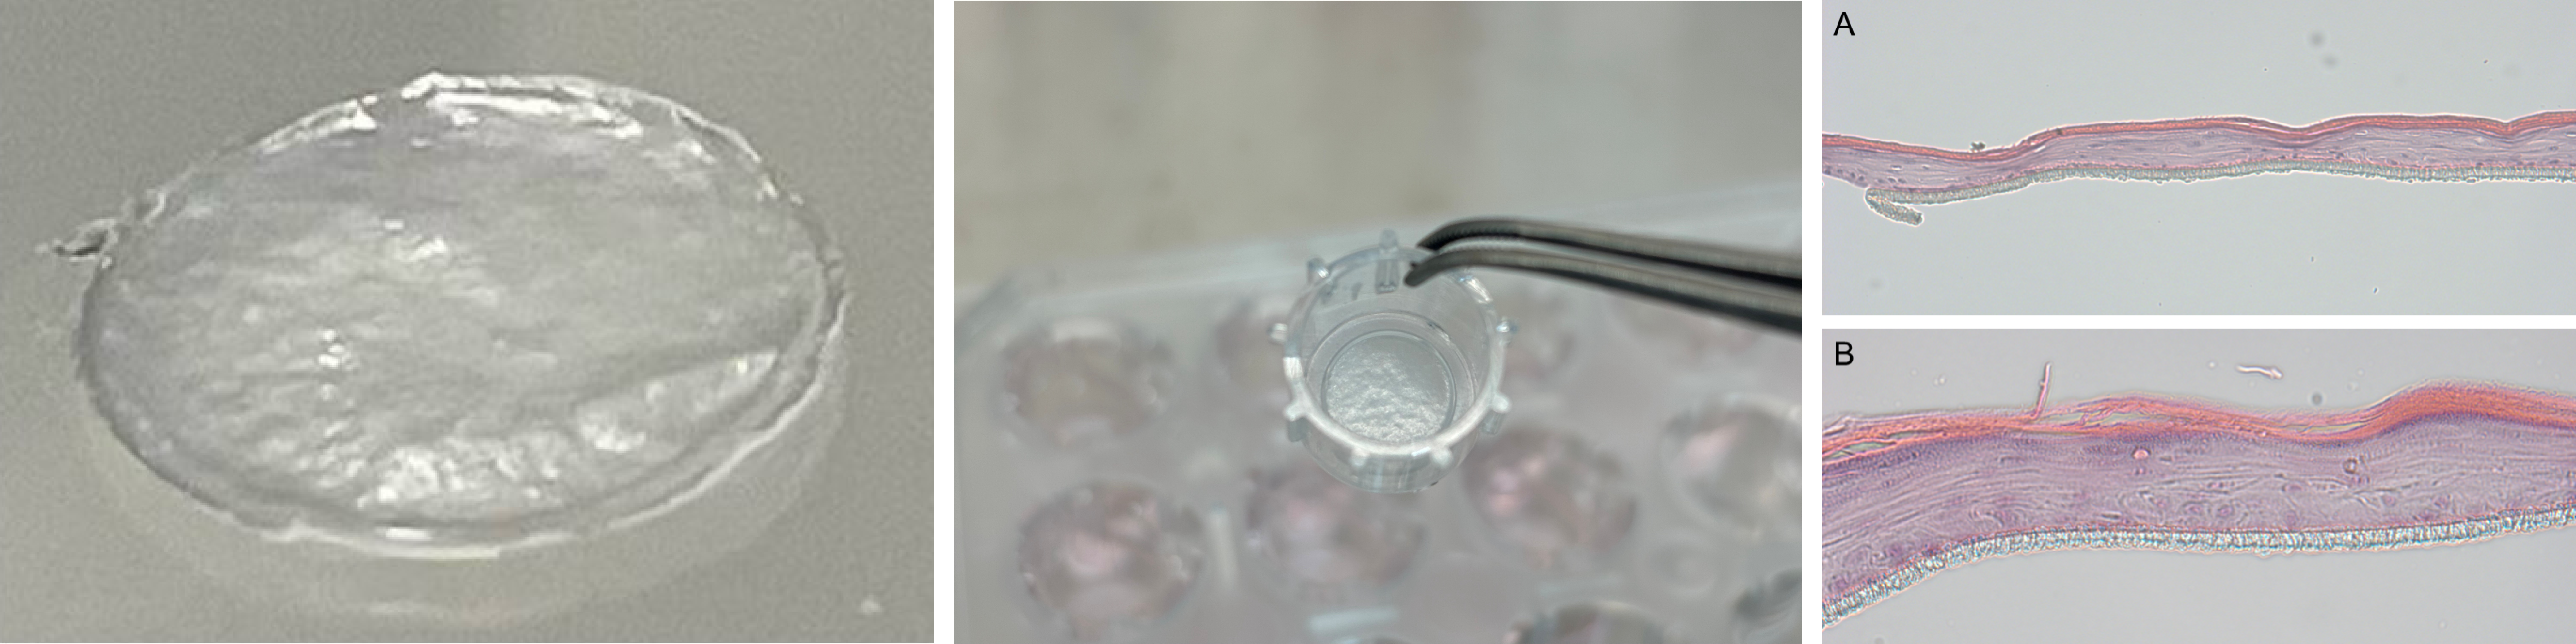

- 培養プロセスの最適化:培養方法を改善することで、通常よりも短い24日間という期間で、皮膚のバリア機能を持つ「角質層」を含む乳児人工皮膚の作製に成功しました。(図1A)

- 高いバリア機能と代謝活性:保湿因子(AQP3)、バリアタンパク(CLDN1)、ケラチン(KRT10)など、皮膚の機能に関わる重要な遺伝子の発現レベルが、従来のヒト表皮角層細胞NHEK(NHEK=Normal Human Epidermal Keratinocyte cells)由来ヒト表皮モデル(NHEK由来RHE)よりも有意に高いことが判明しました。これは、iPS細胞(iPSC)由来RHEが非常に強い生命力と再生能力を持つことを示しています。(図1B)

図1(A).iPS細胞(iPSC)由来RHEおよびRHEの遺伝子発現。(B).HE染色結果並びにフィラグリン・AQP3の発現。(C)免疫蛍光染色結果